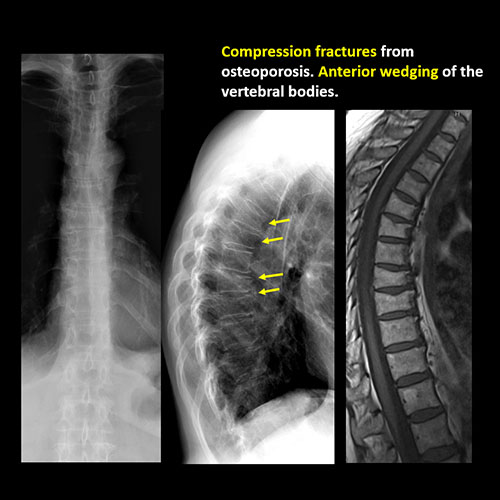

There is anterior wedging and/or compression of a vertebral body. |

No | NA |

There is an oblique fracture with avulsion through the anterior inferior T9 vertebral body. The posterior elements are intact. There is excessive calcification of the anterior longitudinal ligament and there are continuous osteophytes in a pattern consistent with DISH (Diffuse Idiopathic Skeletal Hyperostosis).